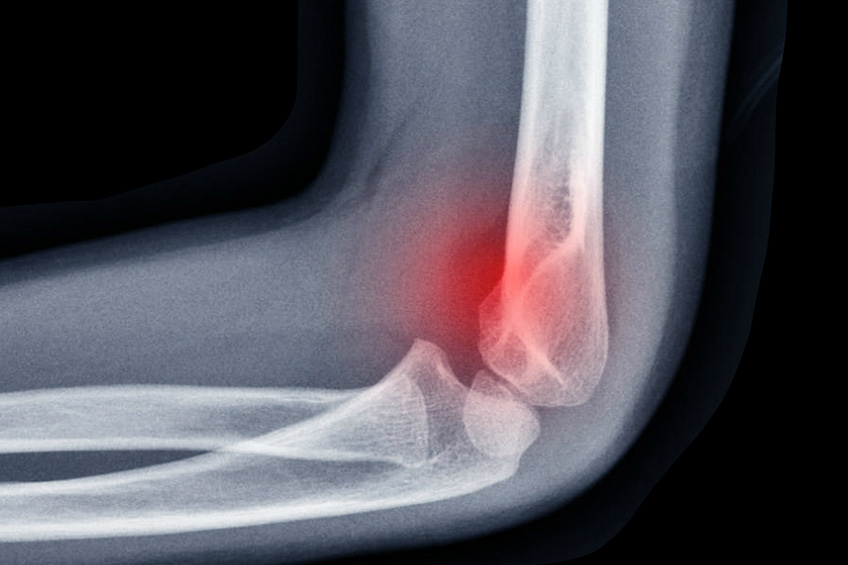

Les fractures autour du coude sont la plupart du temps articulaires pouvant entraîner une raideur à moyen terme et une dégénérescence arthrosique à long terme de cette articulation. De ce fait, le traitement se doit d’obtenir une restitution la plus parfaite et stable possible de l’articulation permettant de réaliser une rééducation précoce et d’éviter les complications.

En sus de ces lésions osseuses, il faut être particulièrement vigilant aux lésions ligamentaires associées qui nécessitent une prise en charge spécialisée.